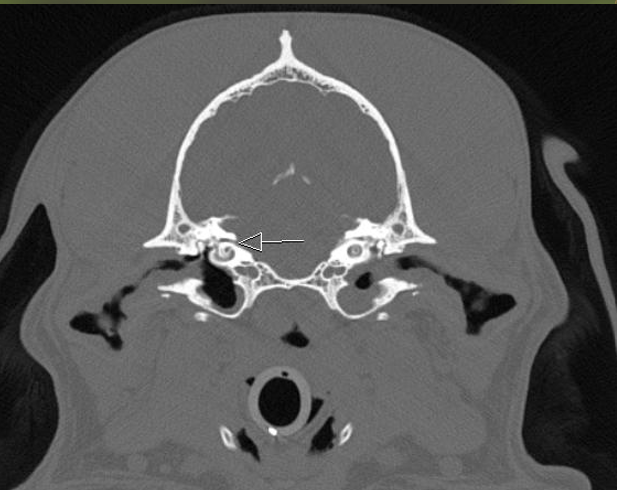

A orbital fissure

B rostral alar foramen leading to alar canal, round foramen inside the skull